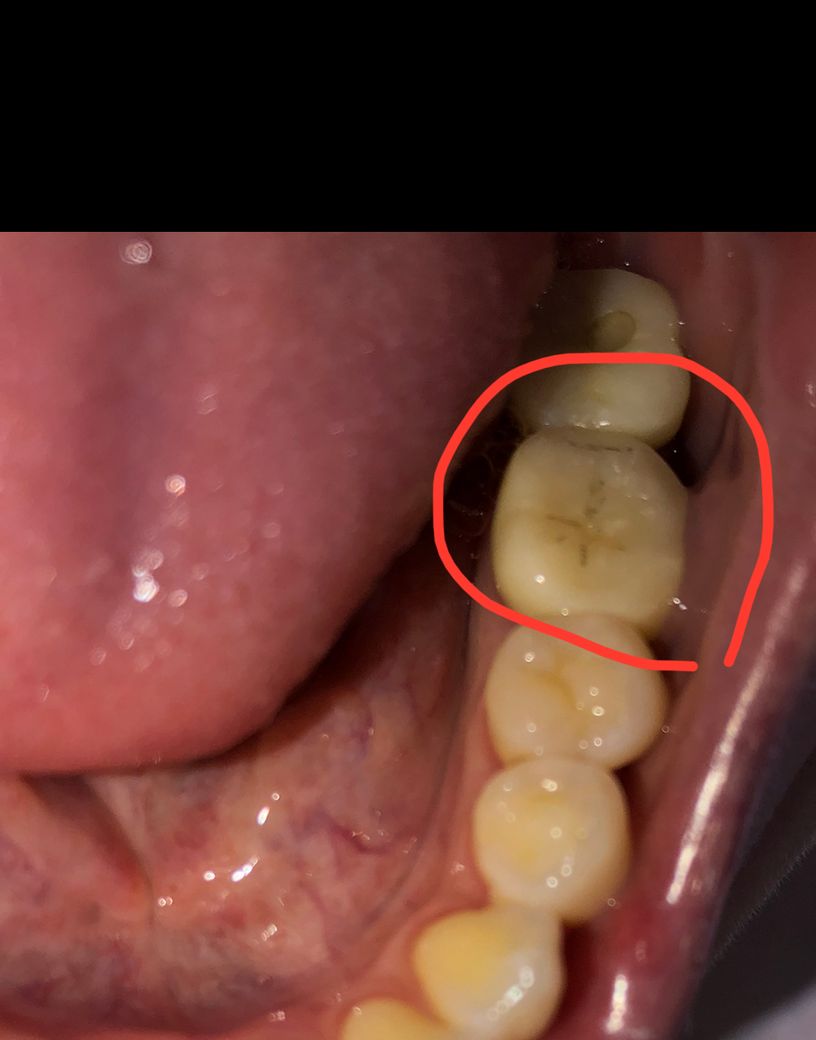

일주일전 완성한 크라운입니다

검은색 금같은게 보이는데 이게 뭔지 궁금합니다 ㅠㅜ

크라운 다시 재작 해야할까요?

모양도 모양인데 이빨에 음식물이 잘껴요 ㅠㅠ

크라운의 보철물 내에 금속이 있기 때문에 검은색으로 보일 수 있습니다.

다시 재작하기보다는, 양치하면서 잘 관리해주시는 것을 권유 드립니다.